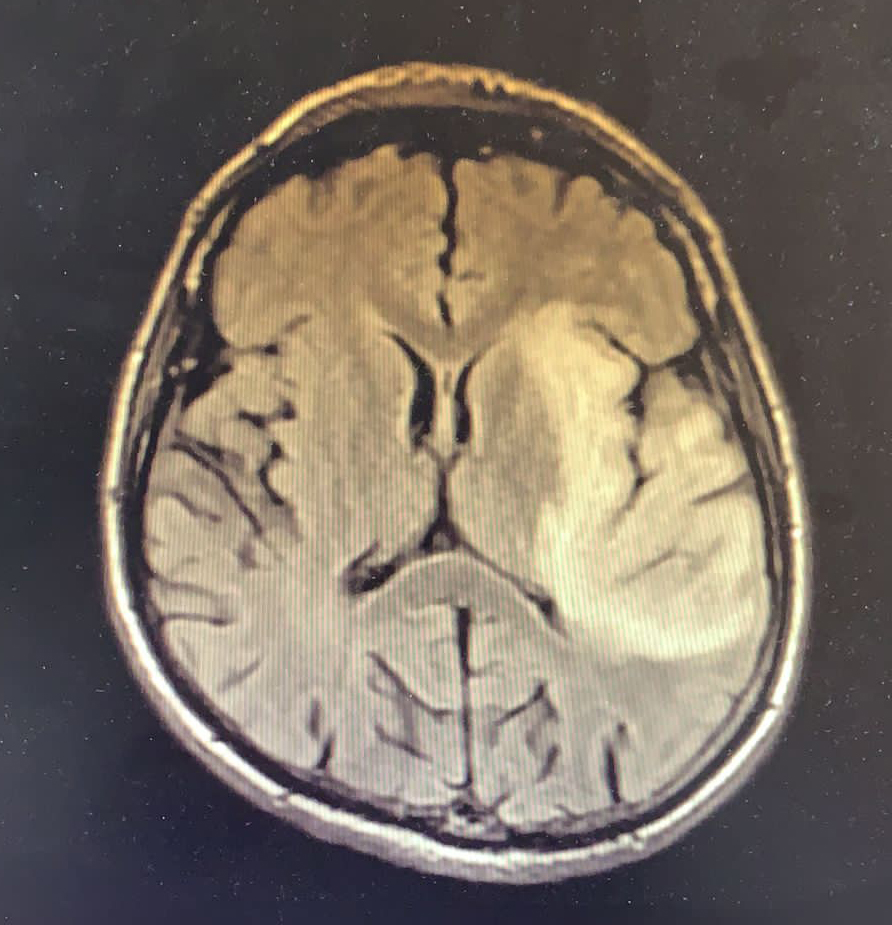

Elli dört yaşında HIV enfeksiyonu tanısıyla bir aydır antiretroviral tedavi (ART) alan erkek hasta, bir haftadır devam eden ateş yüksekliği, üşüme, titreme, bulantı, kusma, iştahsızlık yakınmaları ile kliniğimize başvurdu. FM’de genel durumu orta, şuuru açık, uykuya meyilli, oryante-koopere ve Glaskow koma skalası (GKS) 15 idi. Meningeal irritasyon bulguları negatifti. Dinlemekle solunum sesleri sağ bazalde azalmıştı ve bilateral orta zonda ralleri mevcuttu. Laboratuvarda lökosit sayısı 13.100/uL (%79 PNL) ve CRP 143 mg/L (<5 mg/L), HIV-RNA 718 kopya/ml, CD4 T lenfosit sayısı 126 /mm3 olarak belirlendi. Diğer kan tetkikleri normaldi. Hastanın kontrastlı kranial MR görüntülemesinde sol medial temporal lob düzeyinde, insular kortekste FLAIR sekansta ve diffüzyon ağrılıklı serilerde hiperintens sinyal değişiklikleri izlendi. Sol hipokampusta insüler kortekste kortikal ödem eşlik etmekte olup, her iki singulat girus düzeyinde korteks boyunca lineer difüzyon parlaklığı izlendi (Resim 1). Hastanın beyin omurilik sıvısında (BOS) incelemesinde hücre görülmedi. BOS kültüründe üreme olmadı, mikobakteri-PCR ve viral-bakteriyel menenjit paneli negatif idi.